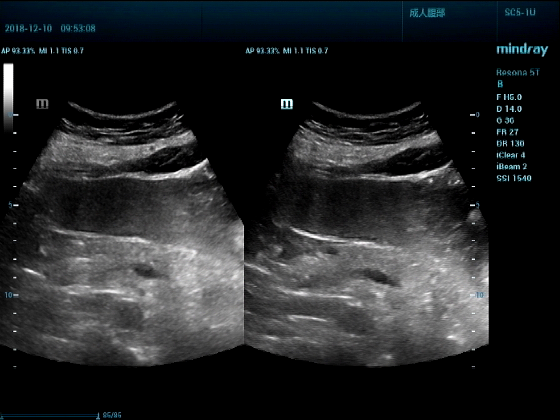

男,81岁,全身浮肿来住院

超声可见:左房,右房,右室明显增大,主肺动脉及右肺动脉增宽,二尖瓣中度反流,三尖瓣重度反流,肺动脉轻度高压,心律不齐

心包积液盆腔积液。淤血性肝增大,肝静脉增宽。(右心衰声像改变)